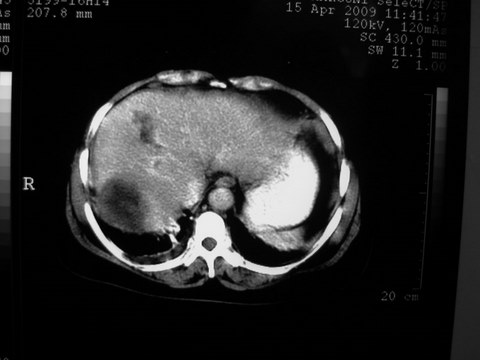

标题: CT19402:肝脏巨大囊实性占位 [打印本页]

标题: CT19402:肝脏巨大囊实性占位

患者 女 51岁 两天前感觉上腹疼,无明显诱因,b超示肝右叶囊实性占位,边缘清楚,其内回声不均匀,ct增强如图,大家看看是什么 ,病人一年前及两月前b超检查只是提示胆囊炎

外院术后,证实肝癌合并出血

特点:1,病灶发展迅速,(2月前正常)[br] 2,囊实性,且并边界清晰光滑,呈右后叶赘生性。囊性区无强化,实性部分较多轻度强化,边界欠清。考虑囊腺癌或囊腺瘤。

出病理 中分化肝细胞癌合并出血